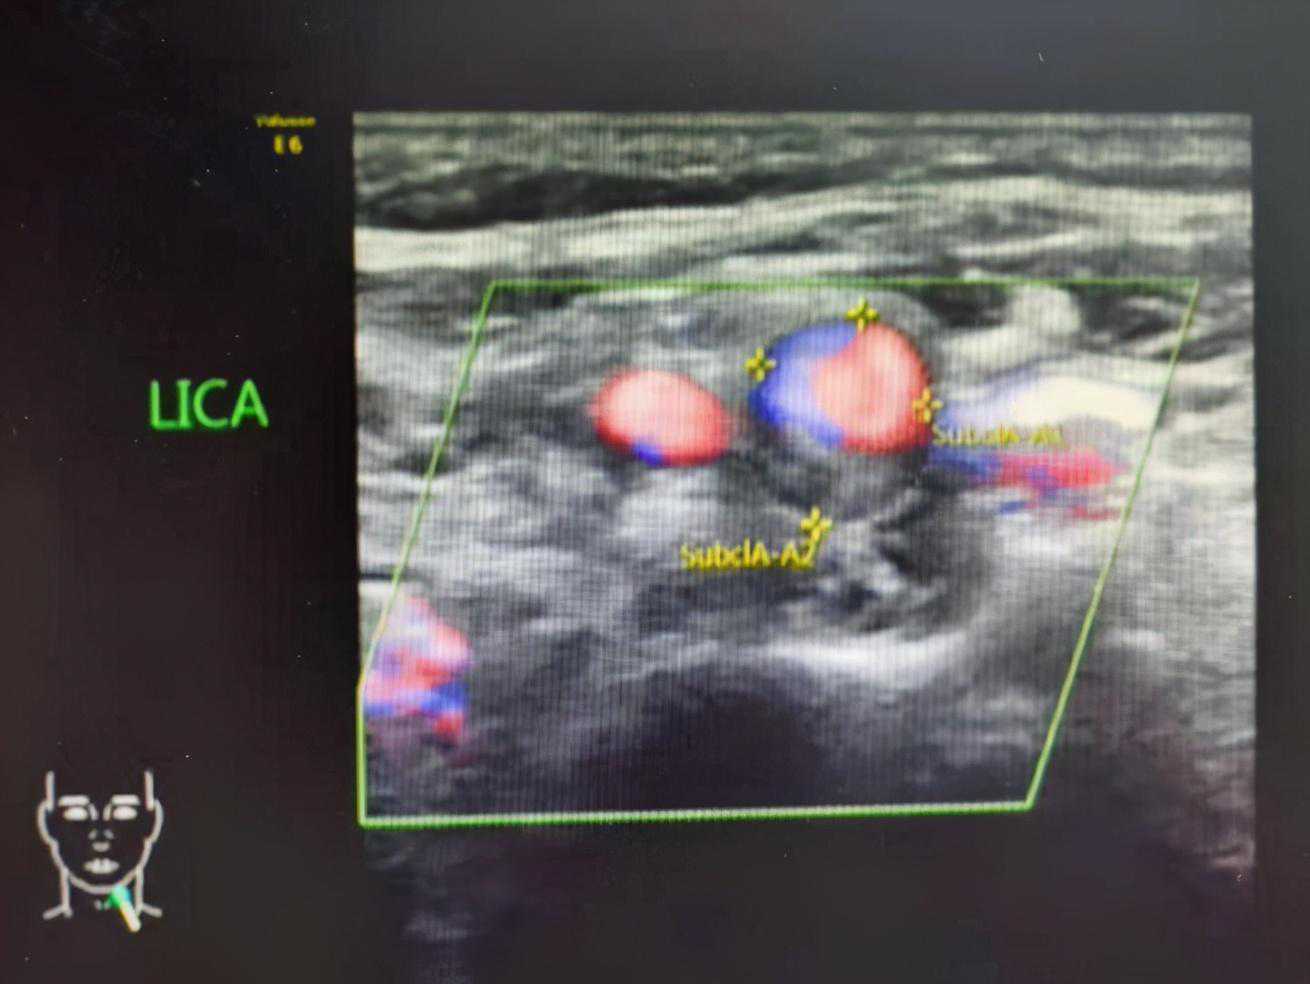

颈部检查

包括甲状腺、颈部血管、淋巴结等;

无需特殊准备;

建议穿着低领上衣,充分暴露颈部。

颈动脉斑块并狭窄